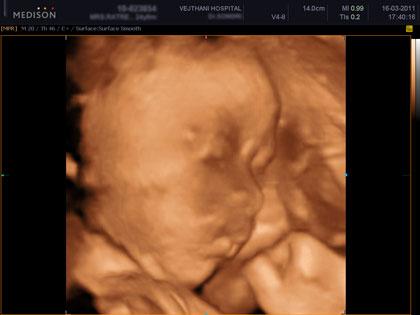

อัลตราซาวด์ 4 มิติ คือการอัลตราซาวด์ 4 มิติ ส่วนใหญ่ก็จะใช้ดูโครงสร้างของเด็ก ดูความผิดปกติ รวมทั้งสามารถดูสีหน้าท่าทางของทารก ซึ่งเป็นอาการตามธรรมชาติของทารก นอกจากนี้ก็ยังสามารถดูโรคที่เป็นความพิการทางโครงสร้าง เช่น ปากแหว่งเพดานโหว่ หัวใจพิการอย่างรุนแรง กะโหลกศีรษะ เป็นต้น ไม่ว่าจะเป็นอวัยวะภายนอกหรือภายใน ก็สามารถดูได้ทั่วทั้งร่างกายของทารก รวมไปถึงการตรวจวัดขนาดของทารก ทั้งนี้จะเป็นประโยชน์อย่างมากกรณีที่พบว่าทารกมีความผิดปกติ แพทย์สามารถวางแผนการรักษาหลังคลอดได้ล่วงหน้า ว่าจะรักษาอย่างไรต่อไป ซึ่งจะทำให้ทารกได้รบการรักษาในทันที

คลิปภาพทารกจากอัลตราซาวด์ 4 มิติ